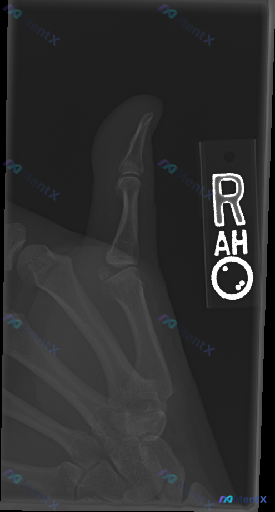

整理到一个有意思的影像病例,虽然只有平片,但讨论点挺多的。 先看核心情况: - 检查部位:右侧大拇指X光(侧位/斜位) - 影像表现:远节、近节指骨及第一掌骨皮质连续,骨小梁清晰,关节对位良好,软组织也没看到明显肿胀或异物 - 影像结论:未见明确骨折、脱位或显著退行性病变 但这份资料的背景是「临床怀...